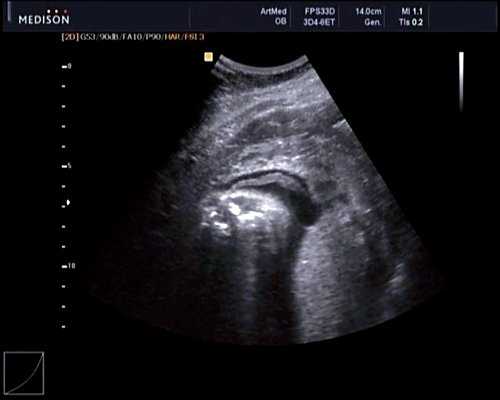

При эхокардиографии изучались четырехкамерный срез сердца плода (рис. 1) и срез через три сосуда (рис. 2). УЗИ проводилось трансабдоминальным датчиком, лишь при необходимости (затрудненная визуализация) использовался внутриполостной датчик. Четырехкамерный срез сердца плода при ультразвуковом сканировании трансабдоминальным датчиком визуализировался в 85% случаев, срез через сосуды - в 73%, при использовании трансвагинального датчика эти цифры существенно возрастали до 100 и 91% соответственно. Оптимизация пренатальной диагностики ВПС может быть достигнута путем строгого соблюдения основных методических правил. При оценке четырехкамерного среза плода необходимо оценить нормальное расположение сердца плода, исключив его эктопию (рис. 3), положение оси сердца плода, что не представляет никаких трудностей, нормальные пропорции и размеры камер сердца, движение створок атриовентрикулярных клапанов должно быть свободным, септальная створка трикуспидального клапана должна располагаться ближе к верхушке сердца (рис. 4). При оценке среза через три сосуда необходимо оценить взаиморасположение сосудов и их диаметр.

Рис. 1. Беременность 12 недель. Четырехкамерный срез сердца плода. Отчетливо видны камеры сердца.